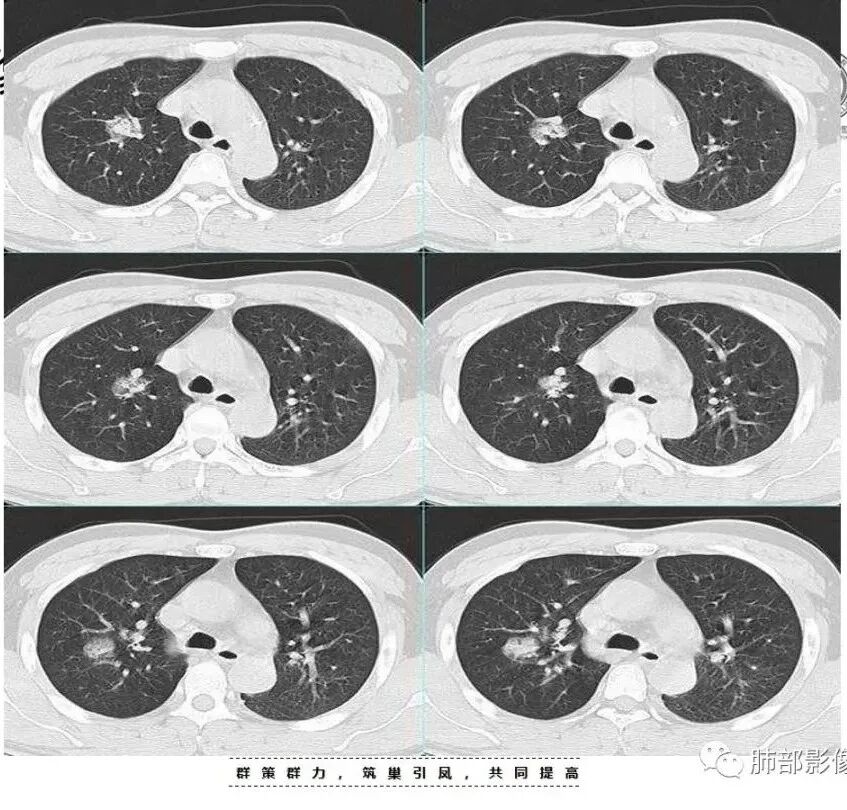

治疗后复查

今天的病例复查很符合金葡菌

左下肺的囊腔呈簇状分布

这是气道早期金葡菌的特点

卜学勇老师对气道来源金葡菌的总结:

金黄色葡萄球菌为厌氧的革兰氏阳性球菌,可产生凝固酶和多种其他毒素及酶,其感染的病理改变中最突出的特点是化脓倾向强,尤其是MRSA肺炎具有起病急,病情进展快,病死率高的特点,早期诊断并进行足量、敏感的抗菌药物治疗对减少其发病率及死亡率具有重要作用。金葡菌肺炎常表现为多种CT征象并存,磨玻璃密度影及斑片影是最常见、最主要的CT表现,肺气囊是典型的影像表现。肺气囊是支气管周围脓肿使终末细支气管和肺泡发生坏死,当与支气管相通后坏死物质排空形成的含气空腔,表现为圆形或类圆形的薄壁空腔,壁厚1—2 mm。部分患者因起病急,使用抗生素较早,在一定程度上也影响了金葡菌感染的程度及转归,表现为磨玻璃样影及斑片影,因此在脓肿基础上形成的肺气囊亦相对较少或出现较晚。

下面是卜老师对气道来源金葡菌的总结: